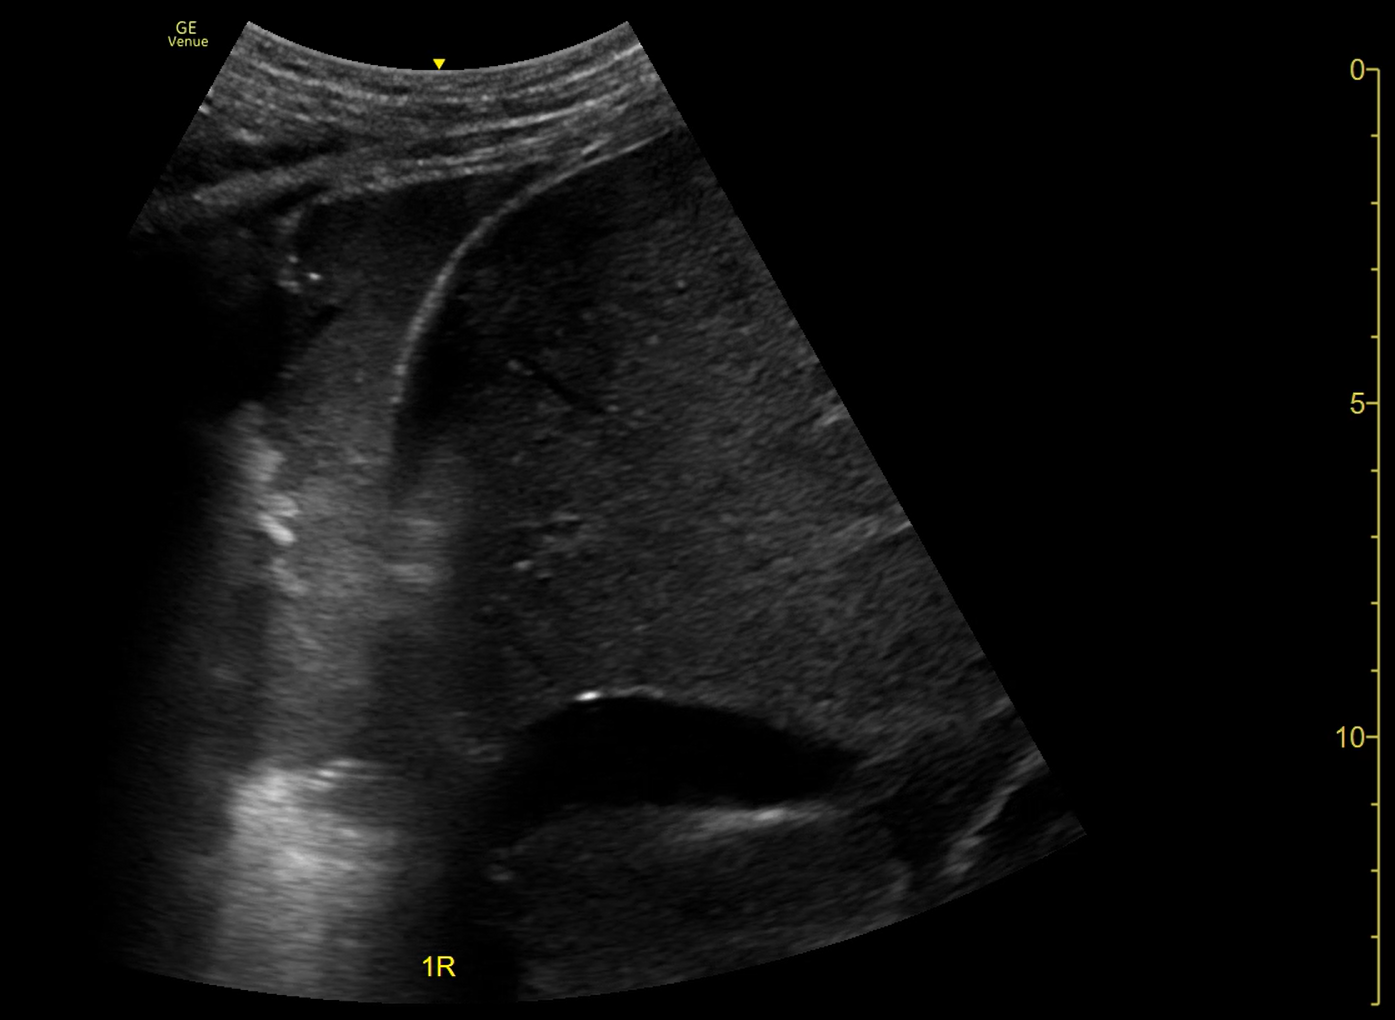

Ecografía pulmonar a pie de cama: Líneas A en ambos ápex y campos pulmonares. Imagen de hepatización pulmonar en base derecha.

Neumonía en lóbulo inferior derecho (LID).

En este caso, la ecografía en la urgencia ayudó a objetivar la condensación neumónica en LID que no se conseguía ver en la Rx torax PA previamente realizada, que junto a la alta sospecha clínica de posible infección respiratoria, ayudó a iniciar el tratamiento antibiótico dirigido y evitar pruebas complementarias innecesarias.